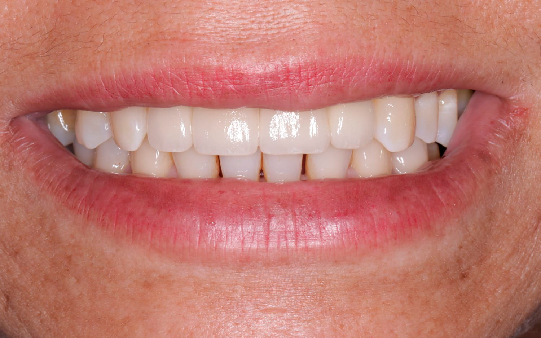

Protocolo em Resina Acrílica: boa estética, acessível, indicado para reabilitações com ótimo custo-benefício.

Esse é o momento perfeito para você trazer o seu sorriso de volta!